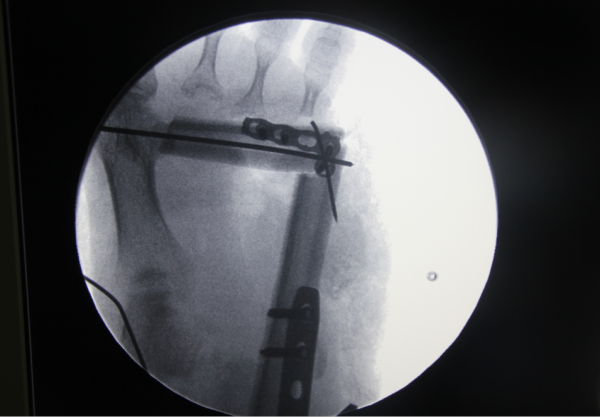

昨天急诊小皮瓣

QQ截图20160919232401.png QQ截图20160919232425.png QQ截图20160919232442.png QQ截图20160919232457.png